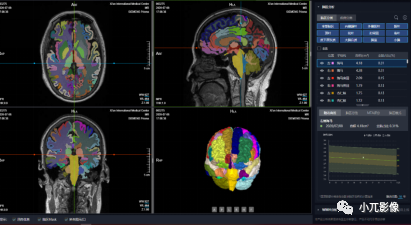

功能性消化疾病患者腦結構精準分析